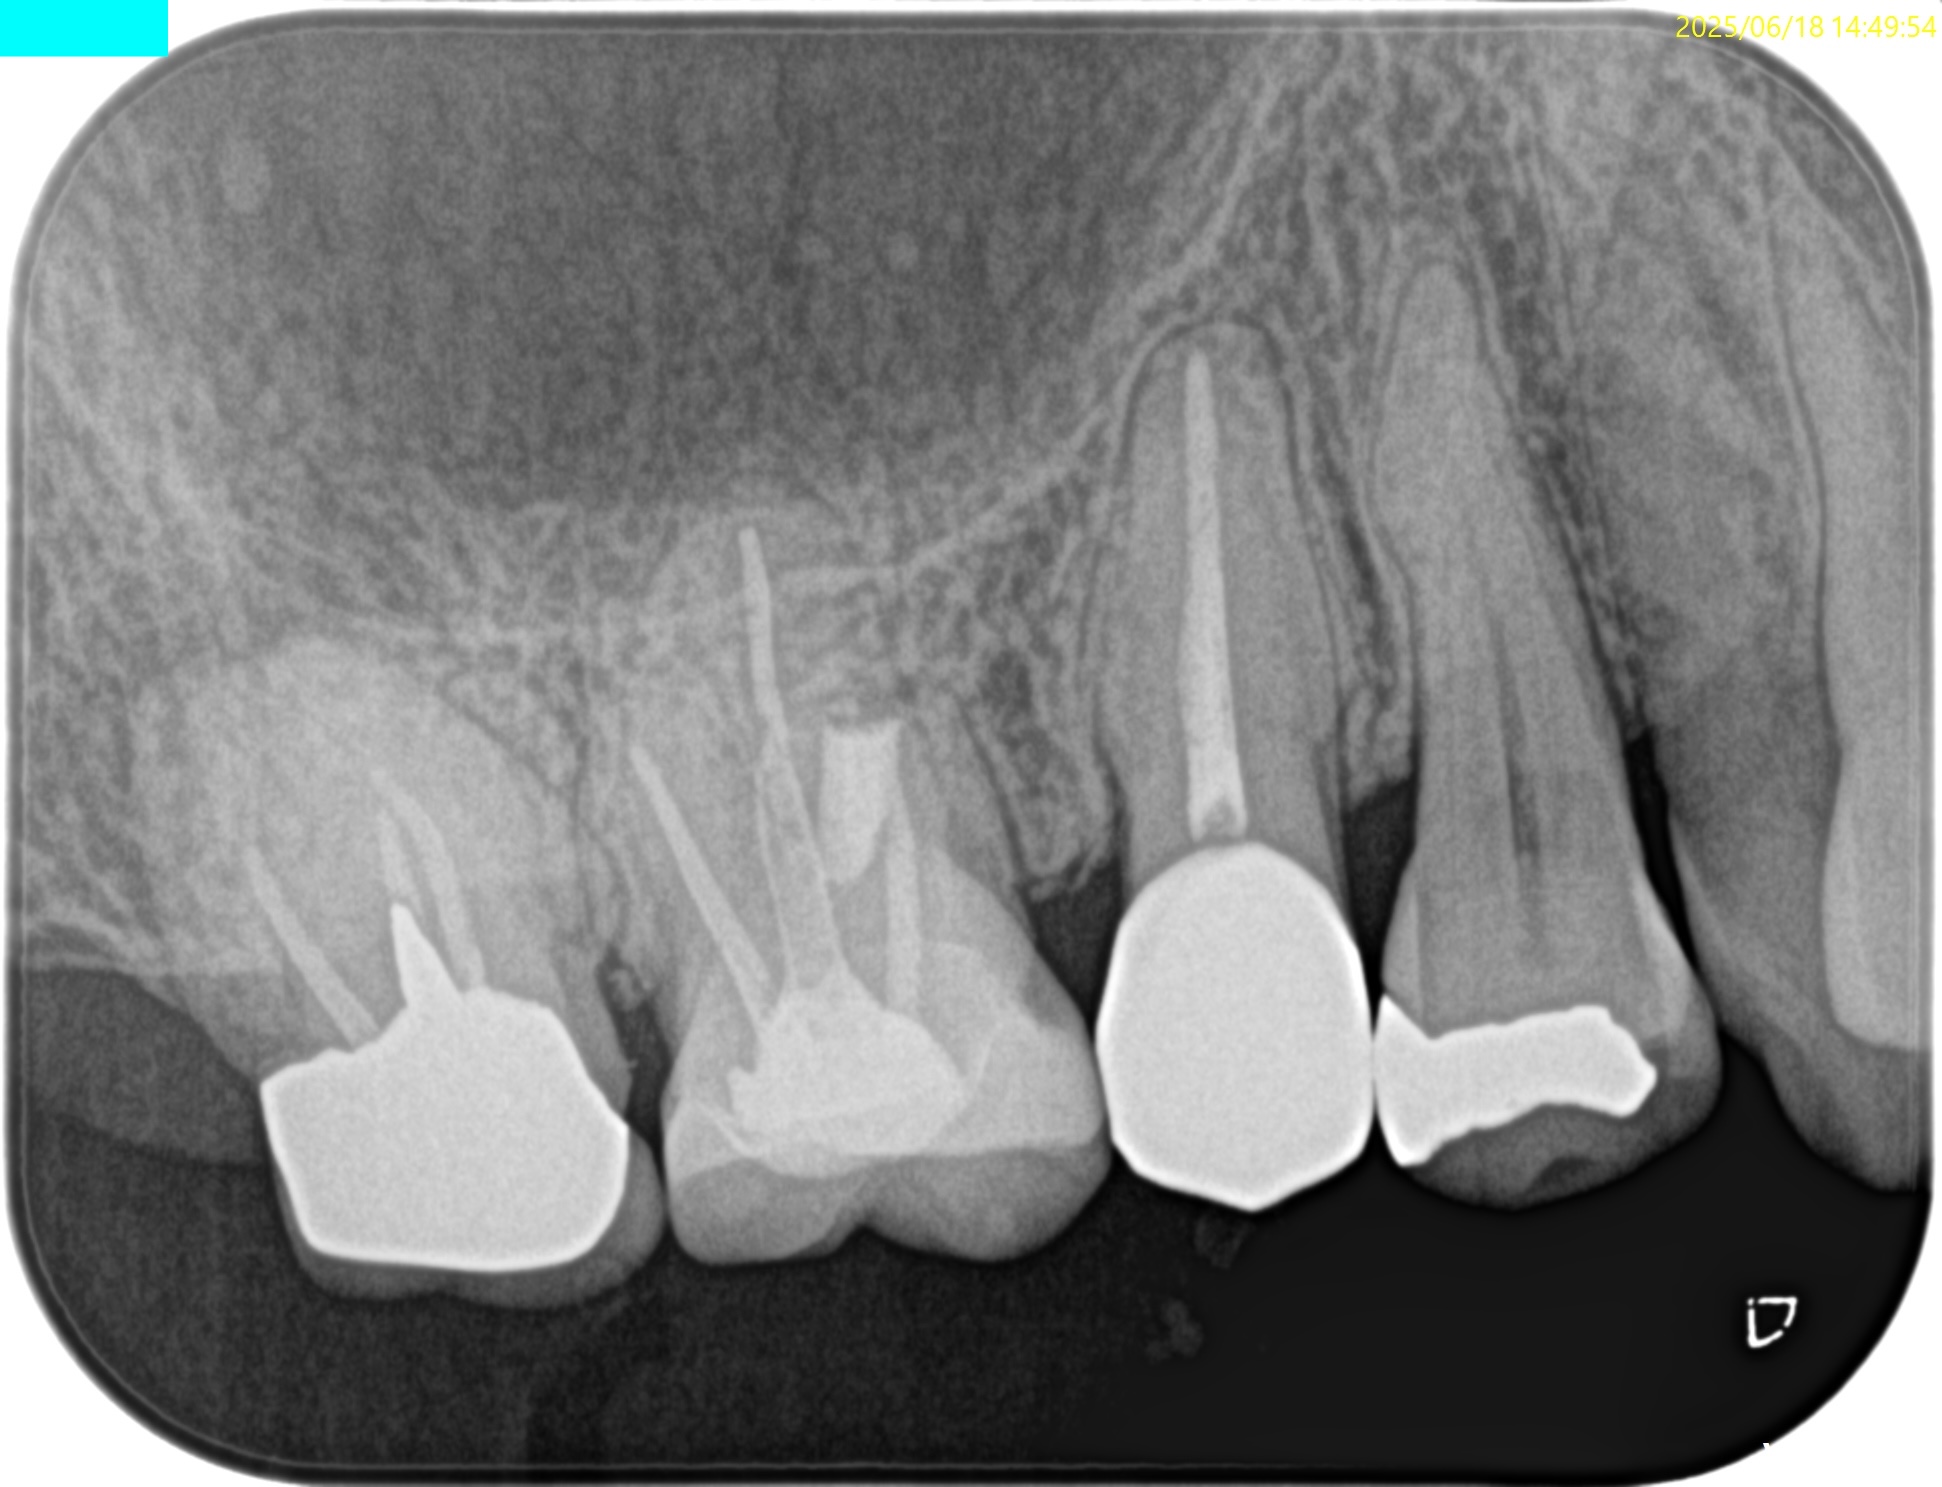

以前、#3 MB Apicoectomyしていた患者さんである。

Apicoectomyした#3は完治したが、#2にも症状があったため、この日に治療となった。

歯内療法学的検査(2025.7.15)

石灰化が進行し穿通が厳しい。

MB,DB,Pと全ての根管は石灰化している。

さらに悪いことには根尖病変がある。